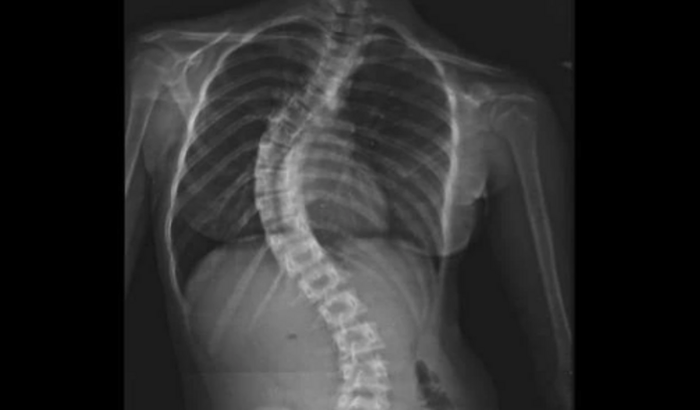

Essa é minha filha , Maria Eduarda 11 anos !

Lembrando que , coloquei esse valor mais o que não for usado eu vou doar pra alguma criança na mesma situação que a minha filha , com esse problema na coluna !